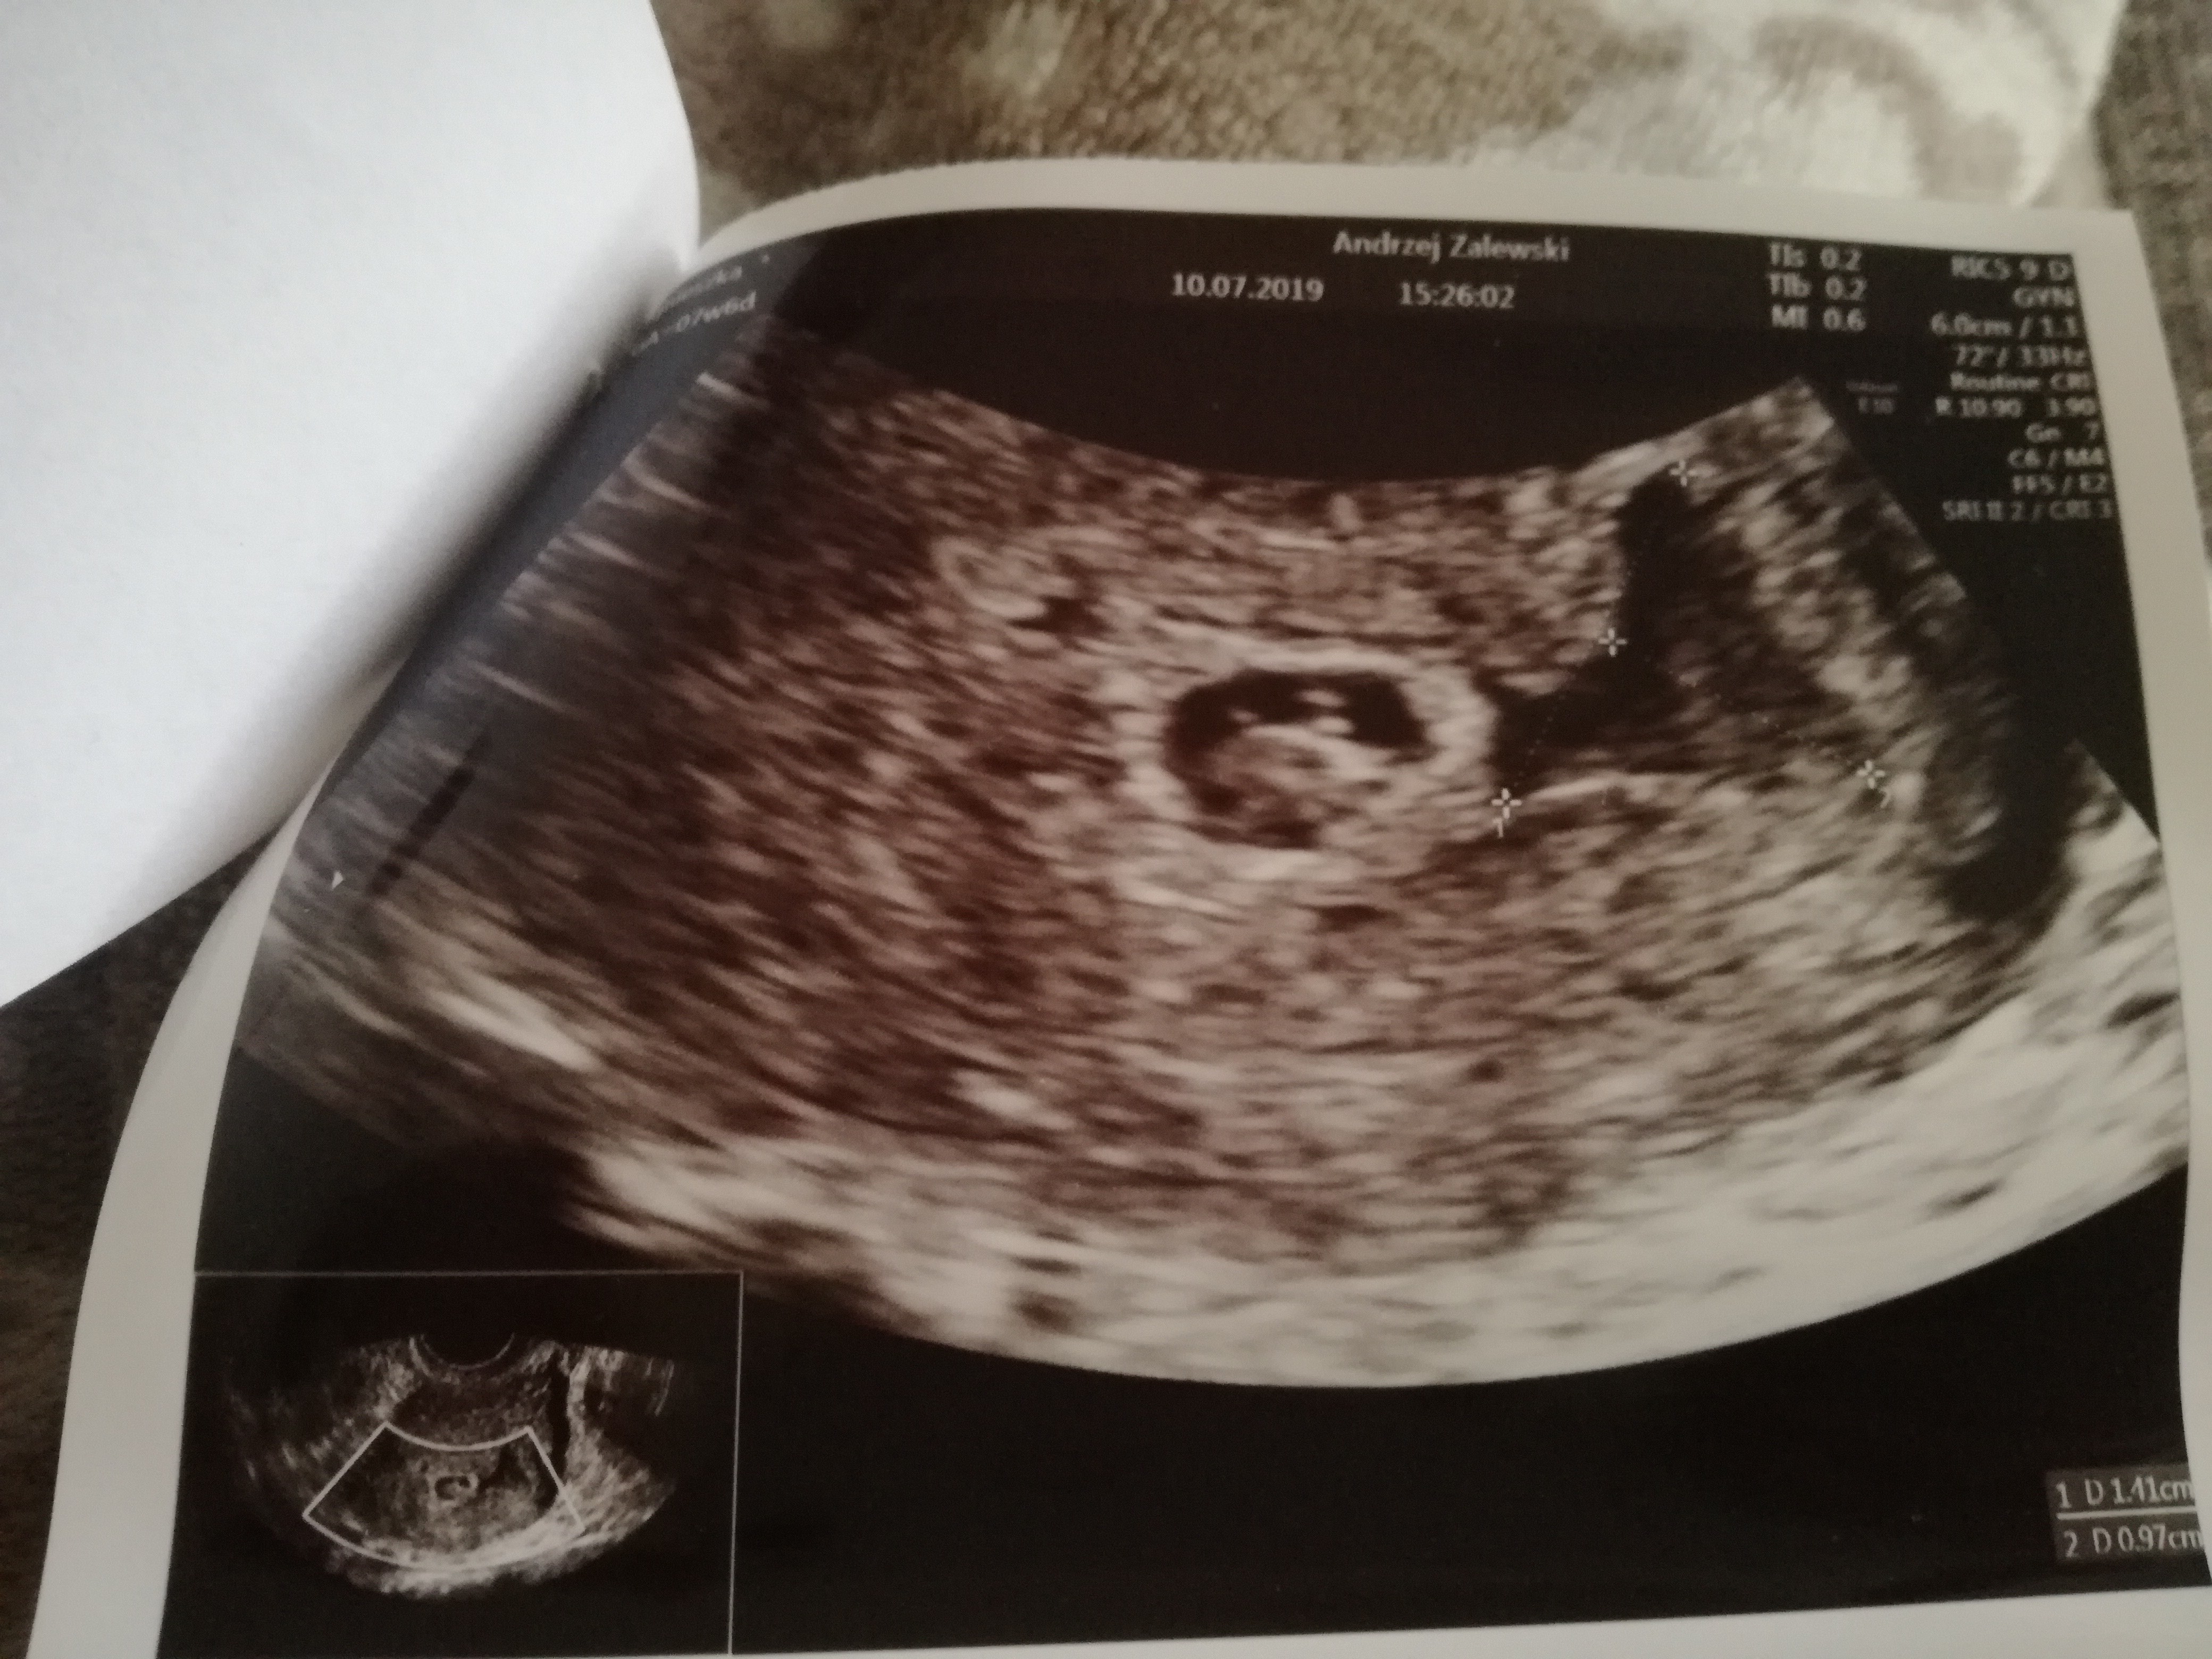

Ginekolog nie dal zadnych szans;( drugi po konsultacji telefonicznej powiedzial ze nie widzi powodu do zmartwien. Crl 8.8mm a pecherzyk 9mm tylko z om 7+6 ale z usg 6+5.

Tak to wyglada, to obok to krwiak